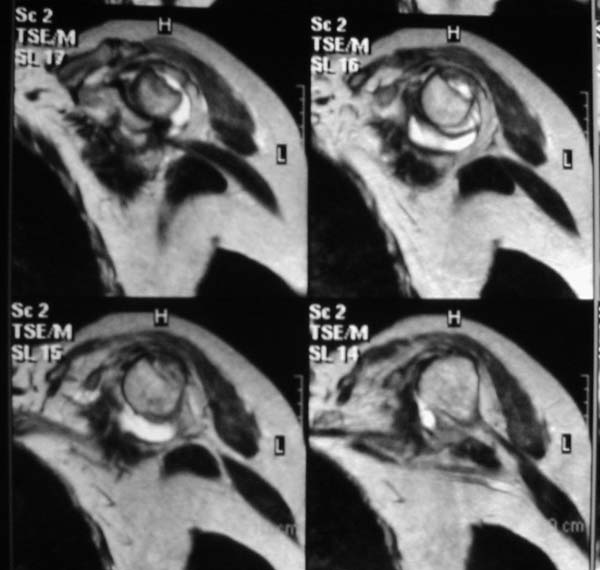

Re: Вывих плеча

"Прицельная" съемка малопонятного очага.

В приложенном файле - МРТ изображение. Более информативно, чем предыдущий вариант? менее? или также?